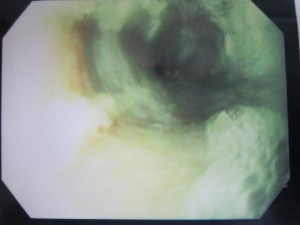

内視鏡でほねっこを胃に押し込みました。

異物はなくなっています。